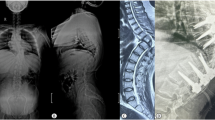

We report the case of a paediatric oncology patient who presented with neurological deterioration secondary to thoracic dorsal spinal cord herniation, manifesting three months after laminectomy for biopsy of a spinal medulloblastoma lesion. We repaired the dural defect using non-penetrating titanium clips to create a secure expansile duraplasty, resulting in radiologically evident reduction of the cord herniation as well as corresponding clinical improvement.

Thoracic dorsal spinal cord herniation is an extremely rare occurrence after spinal surgery. Non-penetrating titanium clips can be used to form a secure expansile duraplasty following reduction of the cord herniation. Successful repair of the dural defect re-anteriorises the cord and can confer neurological benefit.